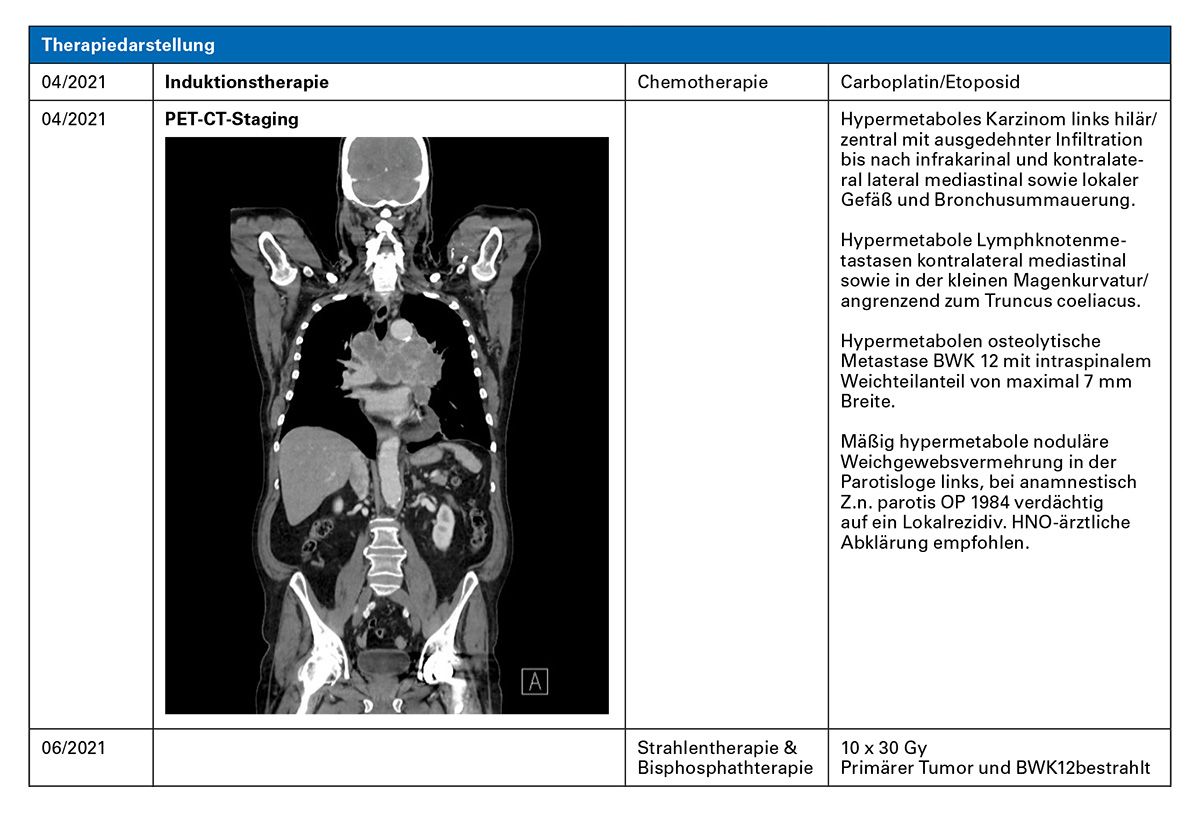

Chemo-Immuntherapie mit Atezolizumab plus Carboplatin-Etoposid, Antiresorptive Therapie mit Denosumab, Antibiotikum-Therapie bei Pneumonie

Fazit: Der Patient hat unter Chemo-Immuntherapie mit Carboplatin/Etoposid und Atezolizumab innerhalb von etwa 4 Monaten eine Krankheitsremission erreicht und ist unter Erhaltungstherapie mit Atezolizumab bis heute stabil. Immunsystem-assoziierte Nebenwirkungen traten nach etwa 18 Monaten auf, ließen sich aber zügig kontrollieren.